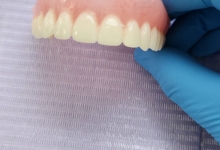

In acest timp are loc procesul de integrare in formatiunea osoasa. Succesul integrarii implantare este dat de catre formarea unei cantitati suficiente de celule osoase in jurul implantului dentar. In functie de necesitatile functionale sau estetice ale pacientului, urmeaza etapa protetica de realizare a lucrarilor de ceramica sau zirconiu. Implantul dentar este foarte important deoarece oasele maxilare se resorb, iar structura fetei incepe sa se modifice. In lipsa dintilor, atat masticatia cat si estetica au de suferit. O igiena necorespunzatoare, fumatul, bruxismul, etc., sunt factori de risc care duc la deteriorarea implantului. In perioada urmatoare dieta pacientului trebuie sa fie moale si la temperatura camerei.

SUPRAPROTEZAREA PE IMPLANT